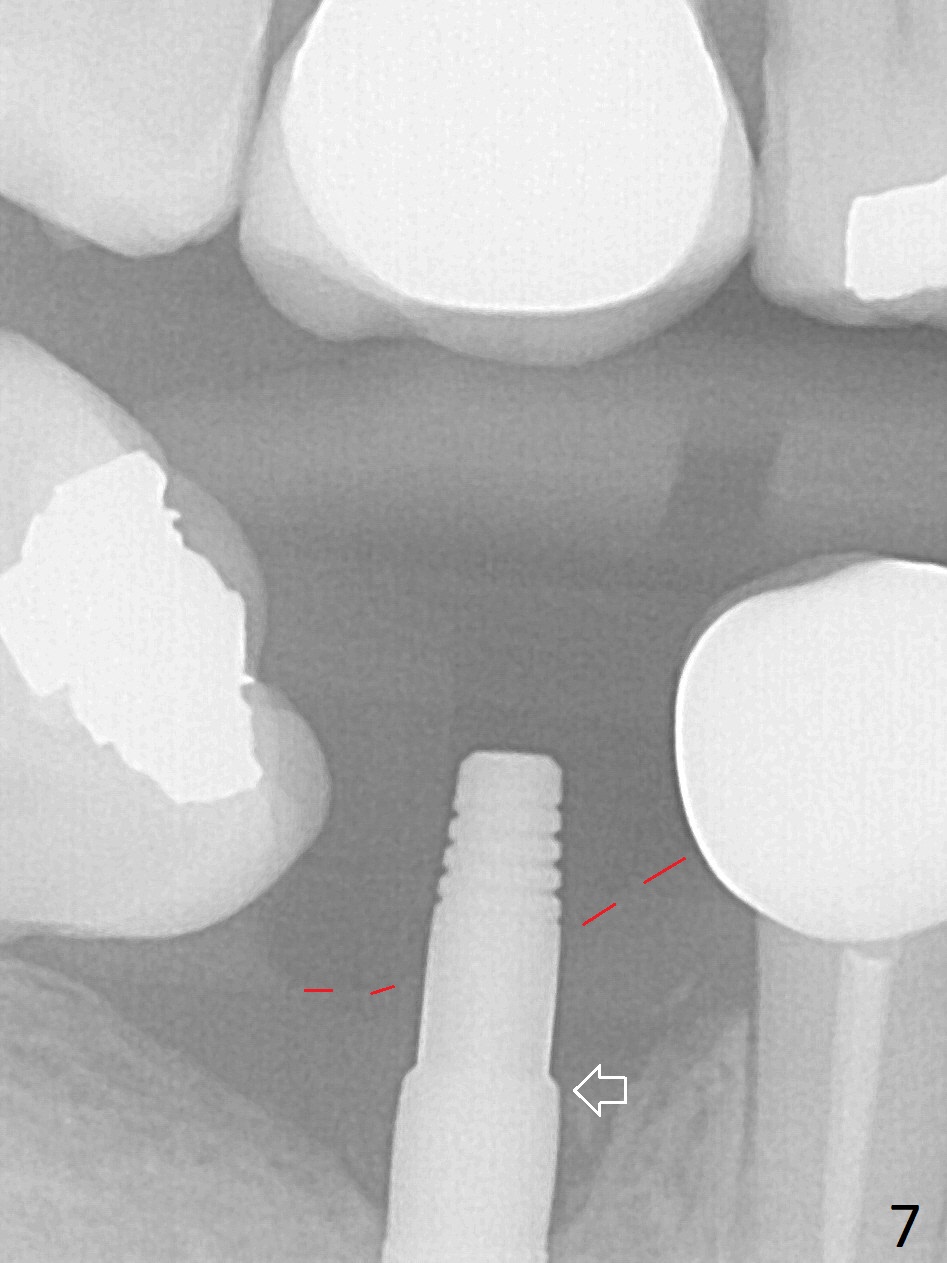

Incision reveals a narrow ridge and a narrow mesiodistal space at #30 (Fig.1).  It seems that a 1-piece implant is indicated.  Due to limited mouth opening, a 1.2 mm drill is unstable in place after use for 10 mm; instead a 1.5 mm drill is able to be inserted for 8 mm (Fig.2).  A 3x10(2) mm 1-piece dummy implant is placed with 40 Ncm at an apparently acceptable level (Fig.3 >).  Clinically a few threads are exposed buccally.  When a definitive implant with the same dimension is inserted with 45 Ncm, it looks seated too deep (Fig.4,5).  The latter is noted after suturing.  The implant is backed up for a few turns so that the length of the abutment appears a little more reasonable.  Introspectively, a 4 mm cuff should have been used after ridge reduction.  Although there is no bone loss 4 months postop (Fig.6), the abutment margin (Fig.7 arrow) is subgingival (red dashed line: gingival margin).  Diode laser is used for gingivectomy prior to impression.  The bone density around the implant increases 11 months post cementation (Fig.8 *), probably related to recurrent #18 infection.  The patient uses floss after meal.